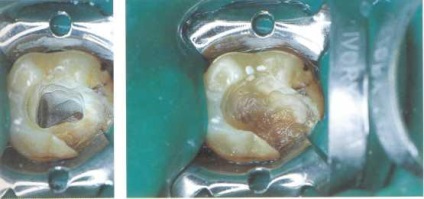

Eltávolítása után az ideiglenes tömítések (pre közgát szabtak) torkolatában a gyökérkezelés volt észlelése felesége sötétszürke devitaliziruyuschaya paszta. Az üreg alján volt a fogszuvasodás.

Balra: miután kiirtás styvshey-paste és cellulóz bővült szája a gyökér ka-fogás.

Ábra. 44. feldolgozása a gyökér-O csatornákat.